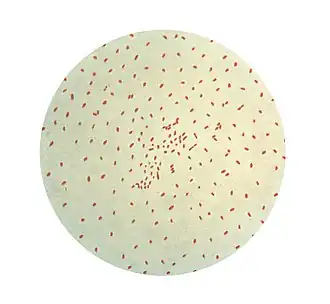

A Bordetella pertussis é um pequeno cocobacilo (meio micrómetro), Gram-negativo e imóvel,[1] sendo um dos agentes causadores da tosse convulsa. É um aeróbio estrito, não fermentador da lactose. Metaboliza aminoácidos, daí que necessite de meios nutricionalmente exigentes para sobreviver. Têm factores de adesão à mucosa as seguintes adesinas: fímbrias, hemaglutininas filamentosas, a porção B da toxina pertussis e a pertactina ou proteína P69. Produz as seguintes toxinas: a toxina pertussis (porção A), a toxina adenilato ciclase, a toxina dermonecrótica, a citotoxina traqueal e ainda LPS e endotoxina, presentes nas bactérias Gram negativo. A toxina pertussis é uma exotoxina do tipo A-B, com a porção B especifica para receptores existentes na célula alvo, para o interior das quais é endocitada. A porção A é a toxina propriamente dita: tem actividade de enzima ADP-ribosil transferase, aumentando o AMPc, um importante mediador intracelular cujo efeito nas células da mucosas brônquica é a produção muito acelerada de muco. A toxina também desregula o macrófagos, resultando em resistência à fagocitose. A espécie Bordetella parapertussis, causa uma doença semelhante, porém menos violenta.